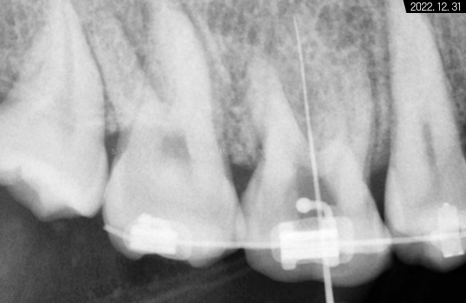

따라서 적정 시기에

CT를 촬영해 치조골 폭과 밀도를

철저하게 분석한 다음 정확한 자리를 선정하고

임플란트 식립을 진행했습니다.

하악 좌측 사랑니 발거 후

임플란트가 필요한 부분들에

픽스처를 견고하게 식립해 드렸습니다.

일정 기간이 지난 후 고정력을 체크하고

지대주에 이어서

크라운까지 예쁘게 수복해 드렸습니다~

크라운으로 감싸고 난 후의 치근단 모습입니다.

정확한 간격으로 견고하게 심어졌으며

주변 치조골 양도 풍부합니다.